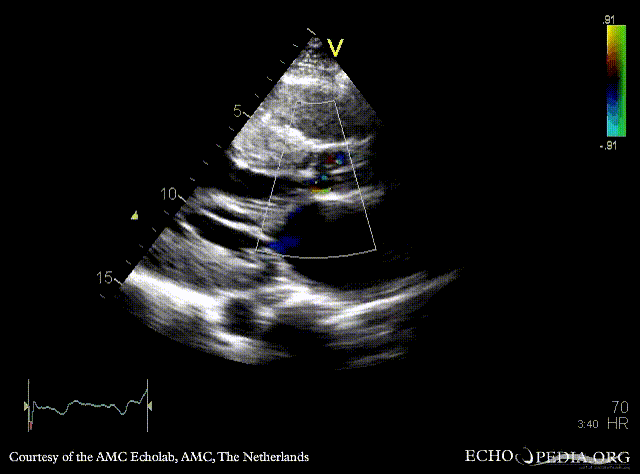

A3CH A3CH with Color Doppler